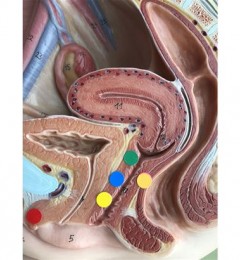

第1个问题就是恶露。在生产后胎盘脱离,阴道会产生分泌物。一般来说产后大概1到4天内会分泌颜色偏红的恶露,后续颜色会慢慢变成暗褐色,再转变成白色。产后妈咪要注意,若恶露出血量多,比方若产妇出血量大到1小时就要换1次的棉垫、夹杂大量的血块,就要立刻就医防治产后大出血。

第2个问题则是乳房肿胀的硬块。乳房肿胀仅次于生产,乳腺管是位于胸部的皮下组织

也是乳汁排泄的管道,当产后奶水太久没有亲喂或者挤出来,就容易造成乳房乳汁堆积,形成肿胀硬的困扰。产后妈咪可以利用疏乳棒,在乳房硬块处加强乳穴点的按摩来疏通乳线。疏乳棒像梳子一样,用手握着朝乳穴点按压,可疏通穴道改善胸部胀痛问题。